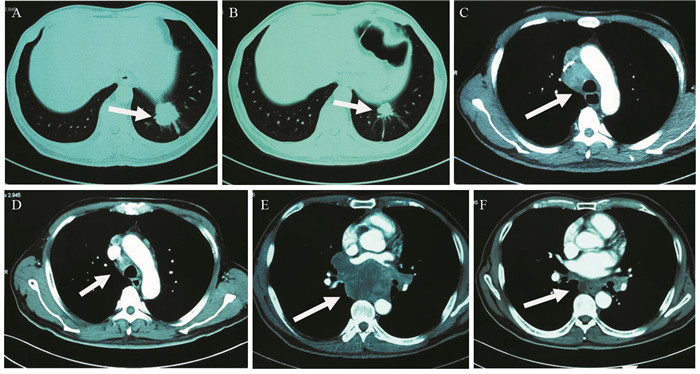

1 病例资料患者57岁,男性,因“进行性吞咽梗阻2月余,咳嗽伴痰中带血一周”于2015年7月16日入院。入院前2月余患者进食干硬食物时感吞咽梗阻。2月以来吞咽梗阻感进行性加重,并逐渐出现咳嗽、咯痰、痰中带血。胃镜提示:食管距门齿27 cm处可见巨大结节样新生物,见图 1A。纤支镜示:左主支气管上段内后壁外压隆起,未见新生物,见图 1B。病理学示:食管内恶性肿瘤倾向低分化癌,见图 2A。免疫组织化学染色:PCK(+)、CK7(+)、TTF-1(+)、CK5/6(-)、P63(-)、CD56(-)、Syn(-)、CgA(-)、NapsinA(-),支持低分化腺癌诊断,但不能确定为肺来源,见图 2A~2D。ALK经免疫组织化学ALK-V及FISH检测(ALK-FISH)均为阳性,见图 2E~2F。食管造影:食管中下段狭窄、管壁僵硬、黏膜破坏,病变长约10.5 cm,见图 3A。胸部增强CT见左肺下叶后基底段约3.7 cm×3.6 cm肿块影,呈分叶状,见毛刺征;纵隔及双肺门淋巴结肿大融合呈团块,最大者短径约3.0 cm;后纵隔约10.1 cm×5.8 cm肿块影,压迫食管,与食管壁分界欠清,见图 4A、4C、4E。头部MRI提示颅内转移瘤。上腹部CT、全身骨显像未见肿瘤转移征象。CEA 31.87 ng/ml,CYFRA21-1 15.49 ng/ml。颈部彩超提示右侧锁骨上区肿大淋巴结,较大约19 mm ×15 mm。入院前2月,体重减轻约20公斤。嗜烟30余年,每天10支。

| A: esophageal lesions (arrow) before treatment (July 23, 2015); B: esophageal lesions (arrow) become smaller after treatment for 11 months (May 13, 2016) 图 3 纵隔及左肺恶性肿瘤伴食管癌待排患者食管造影图像 Figure 3 Digital X-ray barium meal radiography of mediastinal and left lung malignancy coupling with suspicion for esophagus cancer patient' s esophagus |

综上,我们考虑该患者诊断为纵隔及左肺恶性肿瘤:左肺低分化腺癌伴纵隔、双侧肺门及右侧锁骨上淋巴结、脑转移,临床分期Ⅳ期,ALK阳性,食管癌不完全排除。经放疗医师评估,考虑食管穿孔风险大,暂不适宜行放疗。患者美国东部肿瘤协作组(ECOG)评分2分,ALK阳性。根据最新NCCN指南推荐:克唑替尼被批准用于ALK阳性转移性非小细胞肺癌。患者和家属要求行克唑替尼治疗。遂于2015年8月3日开始口服克唑替尼(250 mg,2次/天)治疗。患者耐受良好。服药后,自觉吞咽梗阻、咳嗽、痰中带血症状逐渐消失。至2016年7月,患者已服药11月余,未诉吞咽梗阻等不适,ECOG评分0分。复查食管造影提示食管病变缩小,长度约3.0 cm,见图 3B。胸部CT提示左下肺肿块缩小,约2.4 cm×1.9 cm;后纵隔肿块缩小,约1.7 cm×1.5 cm;纵隔及肺门淋巴结缩小,最大者短径约1.2 cm,见图 4B、4D、4F。参照实体瘤疗效评价标准(RECIST 1.1),临床疗效评价为部分缓解。患者治疗效果显著,支持我们的论断。